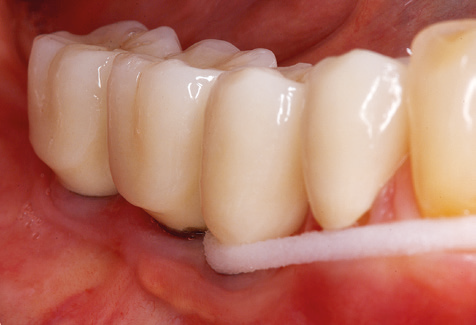

Una buona illuminazione del campo di lavoro facilita notevolmente il processo. Il sistema utilizzato dagli autori ottiene questo risultato grazie a un anello LED 5x integrato nel manipolo. Naturalmente, viene offerta anche una serie di consigli di lavoro per diverse indicazioni. Un inserto diritto, utilizzabile universalmente, è lo strumento di base necessario per la pulizia meccanica dei denti naturali (Fig. 5a e b). Sono disponibili anche inserti curvi, che consentono l'accesso alle forcazioni esposte, per le aree difficili da raggiungere nella regione posteriore (Fig. 6).

Fig. 4: Sonde flessibili con marcature millimetriche sono consigliate per il sondaggio di impianti dentali (ad es. Colorvue Kit PCV11KIT6, HuFriedy). - Fig. 5a e b: Un inserto diritto (1P, W&H Dentalwerk Bürmoos GmbH) è uno strumento adatto per l'uso su tutti i denti naturali. - Fig. 6: Inserti curvi (3Pr / 3Pl, W&H Dentalwerk Bürmoos GmbH) si prestano alla lavorazione di aree difficili da raggiungere del dente e delle superfici radicolari (ad es. Forcazioni). - Fig. 7: L'inserto esagonale conico per la pulizia dell'impianto (1I, W&H Dentalwerk Bürmoos GmbH) consente una pulizia atraumatica ed efficace della superficie della corona e del moncone. - Fig. 8: Le curette in titanio e carbonio sono strumenti adatti per la pulizia manuale delle superfici dell'impianto.